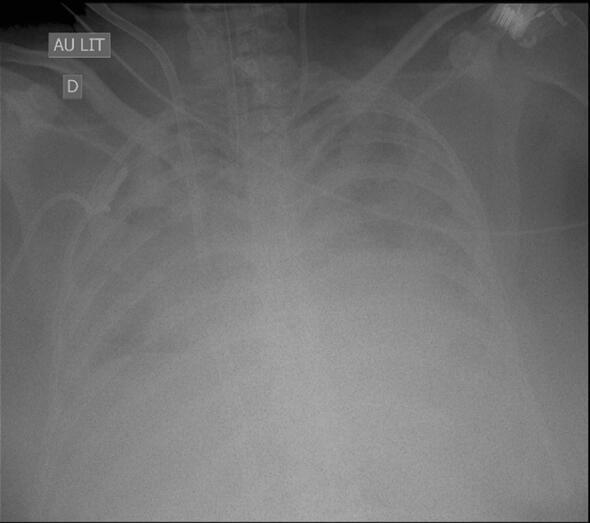

Ventilator-associated pneumonia (VAP) is one of the most frequent ICU-acquired infections. Reported incidences vary widely from 5 to 40% depending on the setting and diagnostic criteria. VAP is associated with prolonged duration of mechanical ventilation and ICU stay. The estimated attributable mortality of VAP is around 10%, with higher mortality rates in surgical ICU patients and in patients with mid-range severity scores at admission. Microbiological confirmation of infection is strongly encouraged. Which sampling method to use is still a matter of controversy. Emerging microbiological tools will likely modify our routine approach to diagnosing and treating VAP in the next future. Prevention of VAP is based on minimizing the exposure to mechanical ventilation and encouraging early liberation. Bundles that combine multiple prevention strategies may improve outcomes, but large randomized trials are needed to confirm this. Treatment should be limited to 7 days in the vast majority of the cases. Patients should be reassessed daily to confirm ongoing suspicion of disease, antibiotics should be narrowed as soon as antibiotic susceptibility results are available, and clinicians should consider stopping antibiotics if cultures are negative.

呼吸机相关性肺炎(VAP)是重症监护病房(ICU)获得性感染中最常见的一种。根据不同的环境和诊断标准,其发病率差异很大,从 5%到 40%不等。VAP 与机械通气时间和 ICU 住院时间延长有关。VAP 的估计归因死亡率约为 10%,外科 ICU 患者和入院时中度严重程度评分的患者死亡率更高。强烈鼓励对感染进行微生物学确认。使用哪种采样方法仍然存在争议。新出现的微生物学工具可能会在未来改变我们对 VAP 的诊断和治疗的常规方法。VAP 的预防基于尽量减少机械通气的暴露并鼓励尽早脱离机械通气。结合多种预防策略的综合方案可能会改善结果,但需要进行大规模的随机试验来证实这一点。在大多数情况下,治疗应限制在 7 天以内。应每天重新评估患者以确认持续存在疾病的怀疑,一旦获得抗生素敏感性结果,就应尽快缩小抗生素范围,如果培养结果为阴性,临床医生应考虑停止使用抗生素。